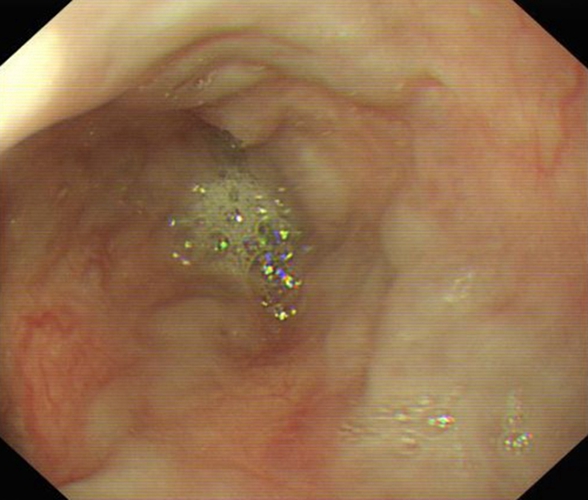

急性胃炎圖片

急性胃炎陽性表現

急性胃炎陽性的表現的

急性胃炎陽性的表現

急性胃炎陽性表現的

急性胃炎的陽性的表現的

急性胃炎的陽性的表現